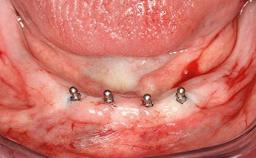

Improving an Existing Implant-supported Denture in an Alzheimer Patient with Bipolar Affective Disorder with Moderate Depression and Dementia

An 83-year-old man presented together with his caregiver at the dental department of the Medical University of Innsbruck, Austria with complaints of swelling in the right maxillary canine area and loss of retention of his 5-years-old mandibular denture. The patient had a significant medical history (20 years) of bipolar affective disorder with moderate depression (F 31.3) and dementia in Alzheimer’s disease (F 00.2). The patient had been in ambulant psychiatric therapy for his depressive illness for the past 20 years. He lived alone and had no children; his sister assisted with daily living. She reported that the patient exhibited compulsive hoarding behavior. In the previous two months, she had noted increasing disorientation and vertigo in the patient. She therefore accompanied him for a medical consultation at the Department of Psychiatry and Psychotherapy of the Medical University of Innsbruck. He was released home after a 6-week inpatient stay.

# of Implants 2

Type of Implants One-Piece

Defining Characteristics Fully edentulous lower jaw to be rehabilitated with two or more implants

Modality 2 interforaminal implants